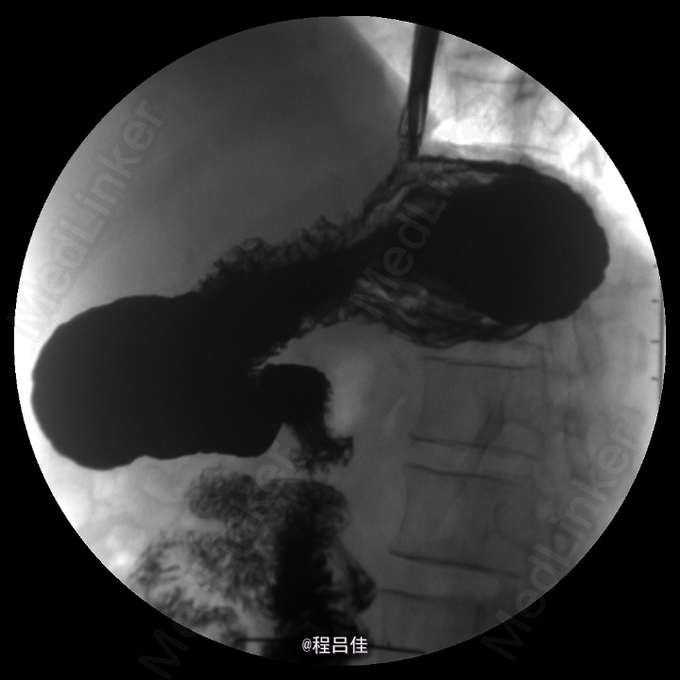

查体:T 36.4℃,P 80次/分,R 13次/分,BP 110/78mmHg。心肺腹阴性。 辅查: 常规胸透示食管:对比剂通过顺畅;食管胃环上提,并可见一浅切迹影,膈上见胃黏膜影,立位时消失。余食管未见明确狭窄、扩张现象,管壁光整,柔软,舒缩功能良好,黏膜皱襞排列规则,未见明确增粗、紊乱、中断现象,未见明确龛影及充盈缺损影;可见少量胃食管返流;球后部扩张,黏膜增粗,扩张以下肠管稍狭窄,但肠壁黏膜规整、柔软,未见明确充盈缺损。结论1.考虑滑动性食管裂孔疝。 2.十二指肠球后部局部稍变窄,黏膜增粗,建议进一步肠镜检查。 3.轻度胃食管返流。

诊断:食管裂孔疝 治疗:完善相关检查,腹腔镜下食管裂孔疝修补+胃底折叠术;术后予以抑酸、促胃排空等治疗。